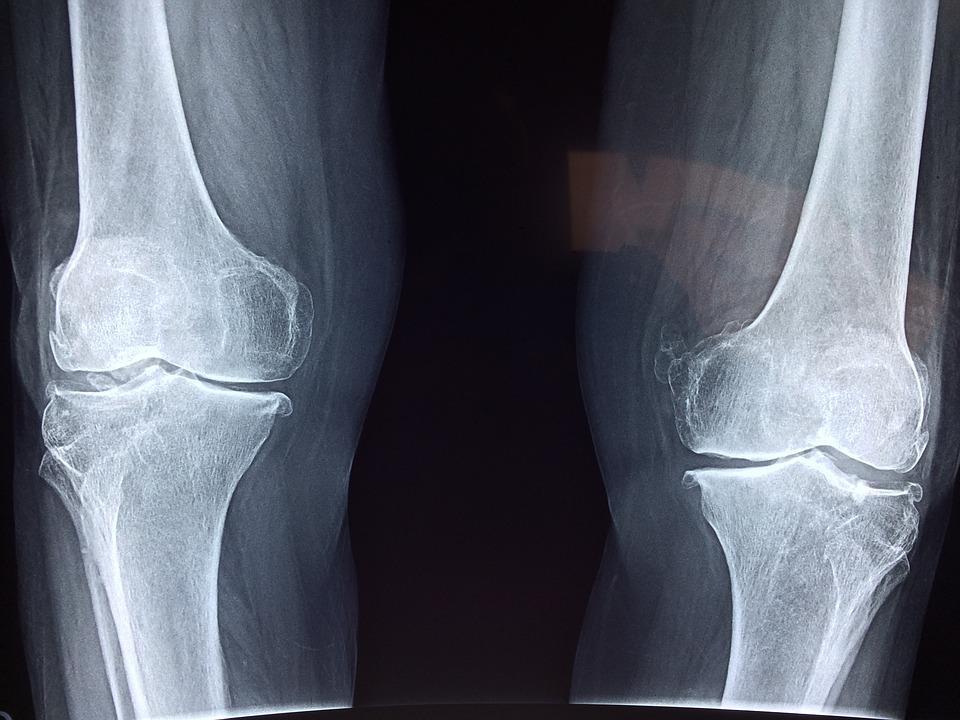

Osteoartritida je chronické degenerativní onemocnění kloubů. Dochází k jejich opotřebení, poškození, které je provázané omezením pohyblivosti a bolestí. Proběhlo již mnoho studií, které zkoumaly bezpečnost a účinnost mezenchymálních kmenových buněk v léčbě osteoartritidy. V této metaanalýze autoři vyhodnotili data z 28 vysoce kvalitních randomizovaných kontrolovaných studií, v nichž bylo dohromady 1 494 účastníků.

Statistické vyhodnocení výsledků 28 studií ukazuje, že léčba osteoartritidy mezenchymálními kmenovými buňkami může zlepšit stav pacientů a je bezpečná.